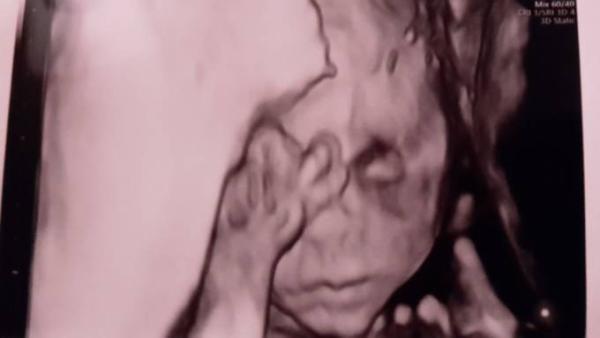

Nach 4 langen Wochen durfte ich heute auch endlich wieder zum Babygucken. Wächst und gedeiht. Aktueller ET 29.03., aber ich kenne mich und laufe eh über den Termin... Alles super und sie sagte sie macht mir auch ein 3D Bild.

Bild zu Heute FA-Termin - Forum für April - Mamis